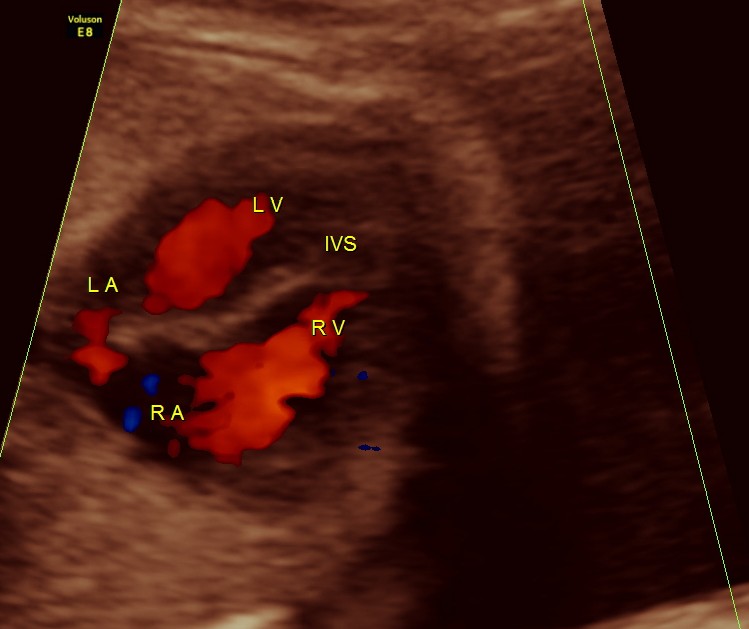

The next 2 images show the findings of the fetal heart. Significant hypertrophy of the septal and apical regions of the Left ventricle are seen.